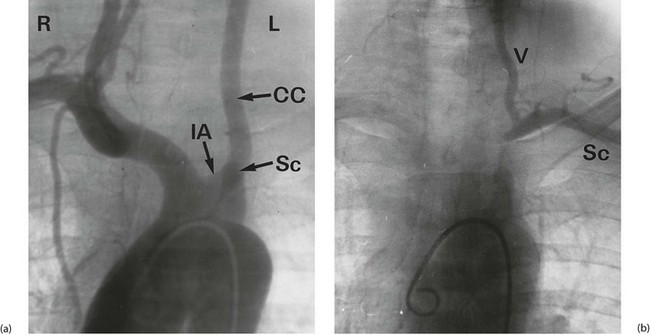

Fig. 42.6 Subclavian steal syndrome

Subtraction angiograms from a 55-year-old house-painter who complained of dizziness when painting walls and ceilings. (a) Aortic arch (with ‘pigtail’ arteriogram catheter visible) showing normal right innominate artery with its subclavian and common carotid branches. On the left, the arterial anatomy is anomalous, with the common carotid CC arising from a left innominate artery IA rather than direct from the aorta (a ‘bovine arch’). The left subclavian artery Sc appears to be occluded beyond a short stump. (b) X-ray exposure taken 4 seconds later; the aortic arch and its branches are now clear of contrast, but contrast has appeared in the left vertebral artery V, flowing downwards from the circle of Willis. This has flowed onwards to fill the left subclavian artery Sc retrogradely. Thus there is complete obstruction of a segment of the left subclavian artery proximal to the origin of the vertebral artery, and the vertebral artery now supplies the left upper limb at the expense of the cerebral circulation. This results in episodes of transient cerebral ischaemia at times of high vascular demand from the left upper limb